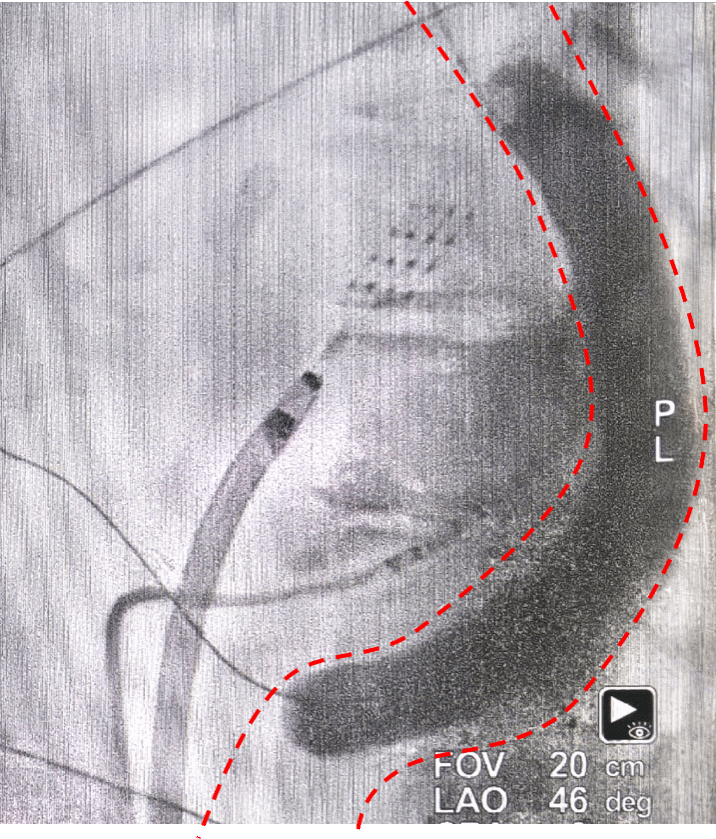

红色虚线处为食管的初始轮廓

红色虚线处为食管牵移后轮廓

按照术前规划,薛嘉虹教授在术中发现,通过显影可见患者食管初始位置紧贴左肺静脉后壁的预定消融线。在X光透视和三维导航系统的精准引导下,团队利用球囊将食管牵拉、移开至安全距离。操作医生得以放心施加充足能量,对左心房后壁实施射频消融,既保证了消融的透壁效果,又全程避免了食管损伤。整个手术过程顺利,患者未出现任何不适,术后临床症状显著缓解。